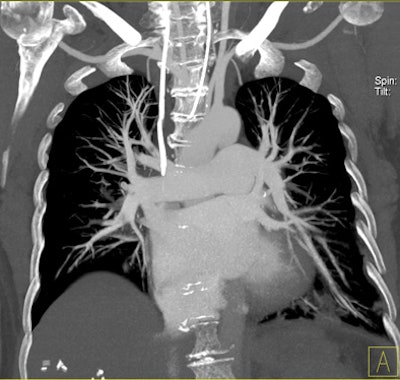

| Patient with bilateral segmental and subsegmental PE and large perfusion defects on dual-energy iodine distribution maps. All images courtesy of Dr. Ralf Bauer. |

Depending on the shape and pattern of the defects at dual-energy CT, perfusion defects due to PE can generally be distinguished from, for example, patchy defects signaling other pathologies of the lung parenchyma, Bauer said.

Dual-energy CT enables the selective display of iodine distribution within the pulmonary parenchyma following contrast-enhanced pulmonary CT angiography, which in turn permits the calculation of perfusion defect (PD) size in patients with suspected PE.

The researchers measured perfusion defect size in the lung parenchyma caused by PE on dual-energy iodine distribution maps, and expressed it in two ways: as absolute quantification (VolPD in mL) and relative to the total lung volume (RelPD in %).